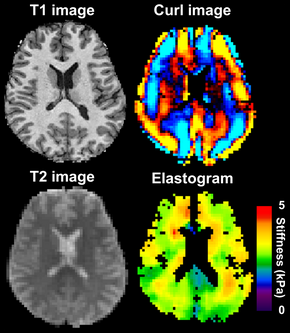

MRE (Magnetic Resonance Elastography) is a technology that combines MRI imaging with low-frequency vibrations to create a visual map (elastogram) that shows the elasticity or stiffness of body tissues. It can help speed up early diagnosis.

Changes in tissue stiffness are known to be associated with various disorders, such as cerebral tumors, Alzheimer's disease and Multiple Sclerosis (MS), making MRE a valuable tool in detecting and monitoring these diseases.

DTI-MRE is a combination of diffusion tensor imaging (DTI) and 3D- vector field data magnetic resonance elastography (MRE).

This scan is able to determine tissue stiffness and diffusion properties. Changes in tissue stiffness are known to be associated with various disorders, such as brain tumors, Alzheimer's disease and Multiple Sclerosis (MS), making MRE a valuable tool in the detection and monitoring of these diseases.